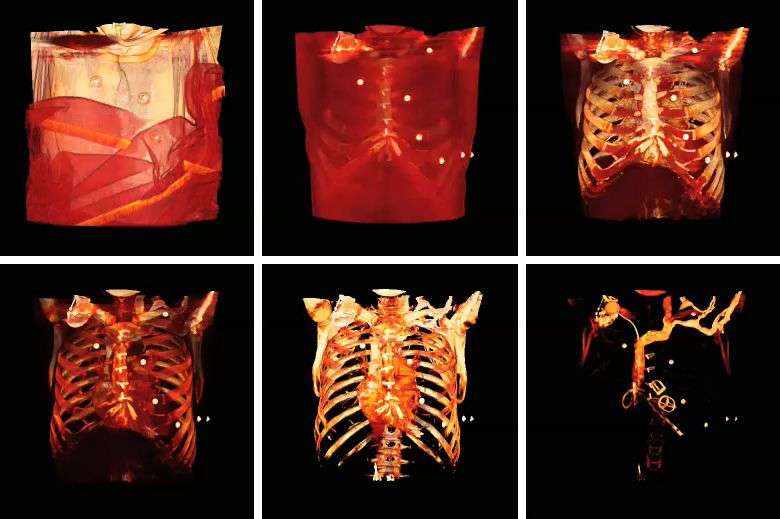

Volume rendering can be applied to the voxel data in the successive rotation manner described for MIPs above, as illustrated by the results in the following figure:

Note that the volume rendering can be contrast enhanced so as to threshold, for instance, through the voxel values to eliminate low attenuating surfaces, as illustrated in the following figure: